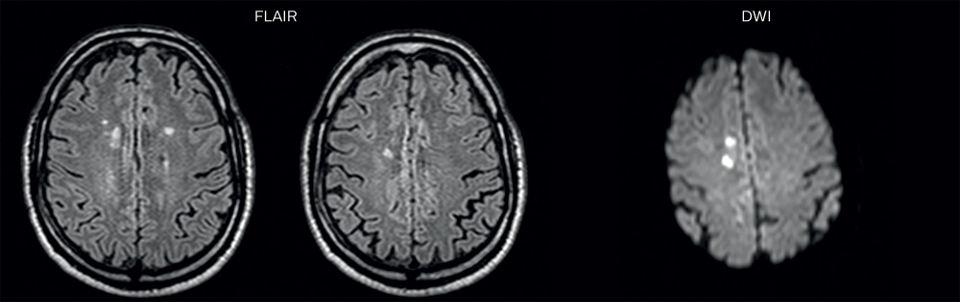

MRI examination with Black Blood imaging

After a conventional routine MR imaging examination, the suspicion of vasculitis arose, therefore we performed an MRI including Black Blood imaging in a separate session. The dedicated ExamCard includes diffusion, FLAIR, MR angiography

using TOF, and 3D T1 MRA with bolus injection. This ExamCard also includes Black Blood imaging before and after contrast. This examination was performed on our Ingenia 3.0T. Black Blood scan time 4:39 min, acquired voxel size 0.75 x 0.75 x 1.0 mm, 21 slices.

On FLAIR images we can see some nonspecific high signal abnormalities in frontal white matter bilaterally. On DWI we can see acute ischemic lesions which appear with high signal intensity. Arrows show vessel wall enhancement which appears concentric and homogeneous in different cerebral territories.